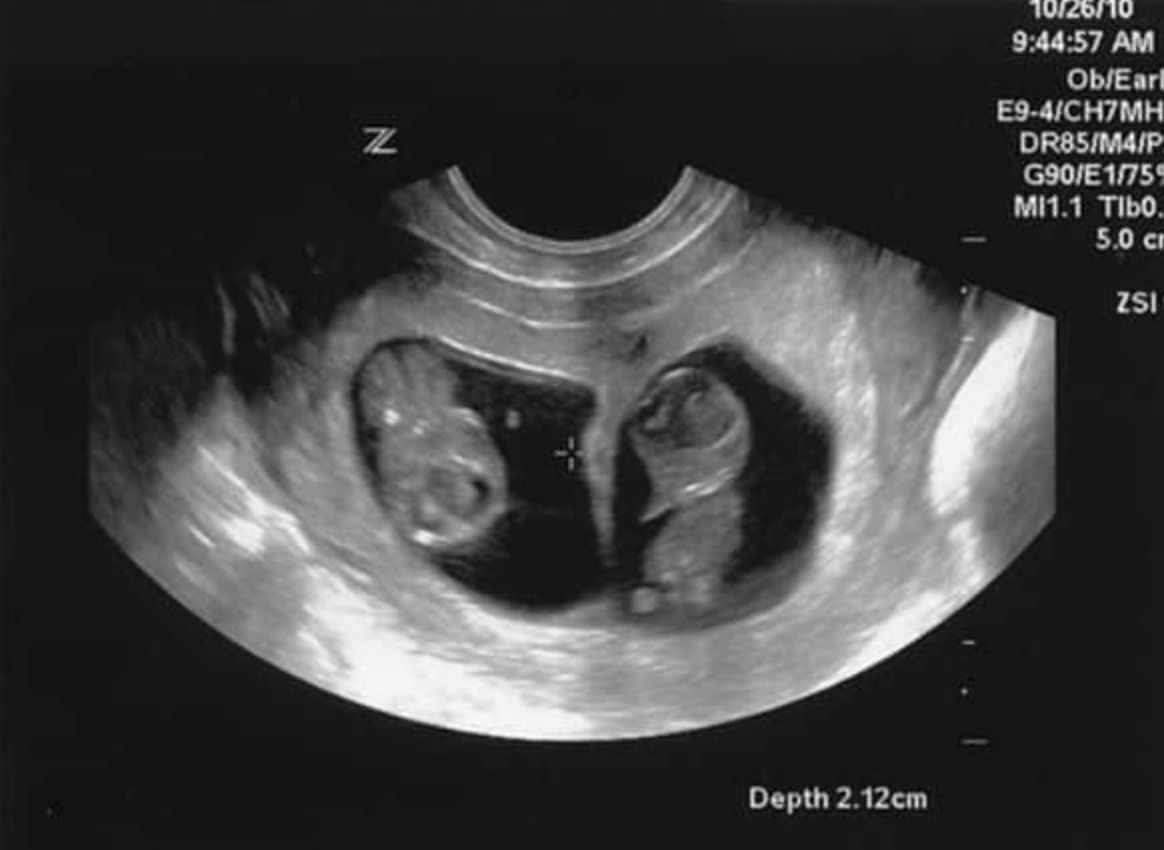

Les médecins ont averti Nicole que les médicaments qu’elle prenait pour sa maladie seraient nocifs pour le bébé, et lui ont déconseillé de tomber enceinte. Lorsqu’elle a suggéré d’arrêter son traitement, ils lui ont dit que cela pourrait lui être fatal. Le taux de mortalité du PTT atteint 95% lorsque la maladie n’est pas traitée.

Nicole s’est retrouvée face à un ultimatum. Est-ce qu’elle risquerait sa vie pour tomber enceinte ? Rendez-vous à la page suivante >>